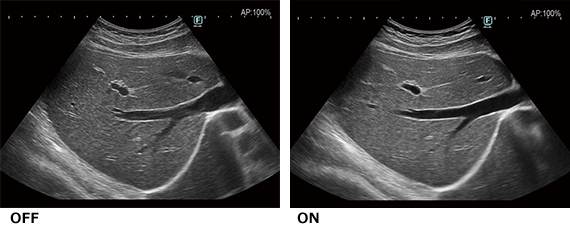

AI技術※を活用したノイズ除去技術「DeepInsight技術」

画質処理開発においてAI技術※を使用したDeepInsight技術は,膨大な情報から必要な情報のみを抽出し,ノイズに埋もれていた微細な組織や複雑な組織構造をより明瞭に表現することが可能となりました。より自然な表現で組織を描出します。

※AI技術のひとつである機械学習を用いて開発・設計したものです。実装後に自動的に装置の性能・精度は変化することはありません。